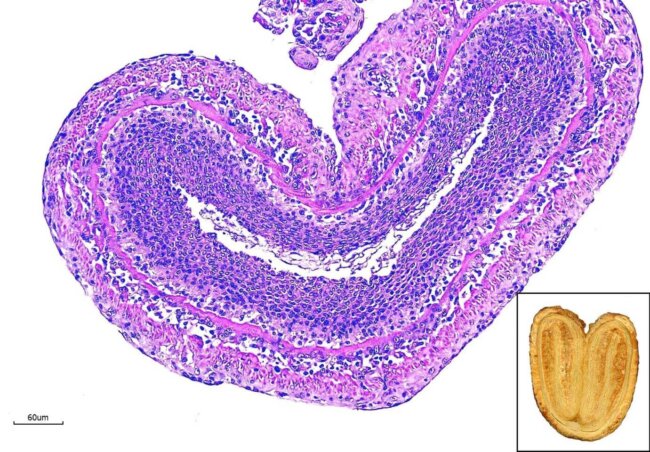

今天想來點….蝴蝶餅??